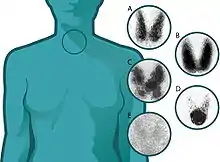

.jpg.webp)

El exceso de HT se debe a una enfermedad primaria del tiroides, con lo que estas se elevan en sangre y suprimen la producción de TSH. Las enfermedades pueden ser:

- Enfermedad de Graves-Basedow: se trata de una enfermedad de etiología autoinmunitaria en la que se producen inmunoglobulinas contra el receptor de la TSH que estimula la producción de HT y el crecimiento difuso del tiroides. La gammagrafía tiroidea demuestra la existencia de un bocio con captación difusa. Se desconoce qué desencadena la aparición de estos anticuerpos, aunque existe una propensión familiar. La enfermedad se manifiesta con exoftalmos, dermopatía infiltrante o mixedema pretibial.

- Adenoma tiroideo tóxico: Es un tumor benigno del tiroides que se manifiesta como un nódulo único que produce HT en exceso. El resto de la tiroides se atrofia al suprimirse la producción de TSH, la gammagrafía tiroidea muestra la presencia de un nódulo mientras que el resto de la tiroides no capta yodo.

- Bocio multinodular tóxico o enfermedad de Plummer: se debe a un crecimiento policlonal de células tiroideas que se manifiesta con múltiples nódulos de diferente tamaño, consistencia y actividad. La gammagrafía tiroidea muestra numerosas áreas con captación variable

- Tiroiditis: se puede producir una tirotoxicosis por una brusca destrucción de la tiroides con la salida de las HT almacenadas a la sangre, el tiroides inflamado no capta yodo radioactivo o lo capta escasamente.